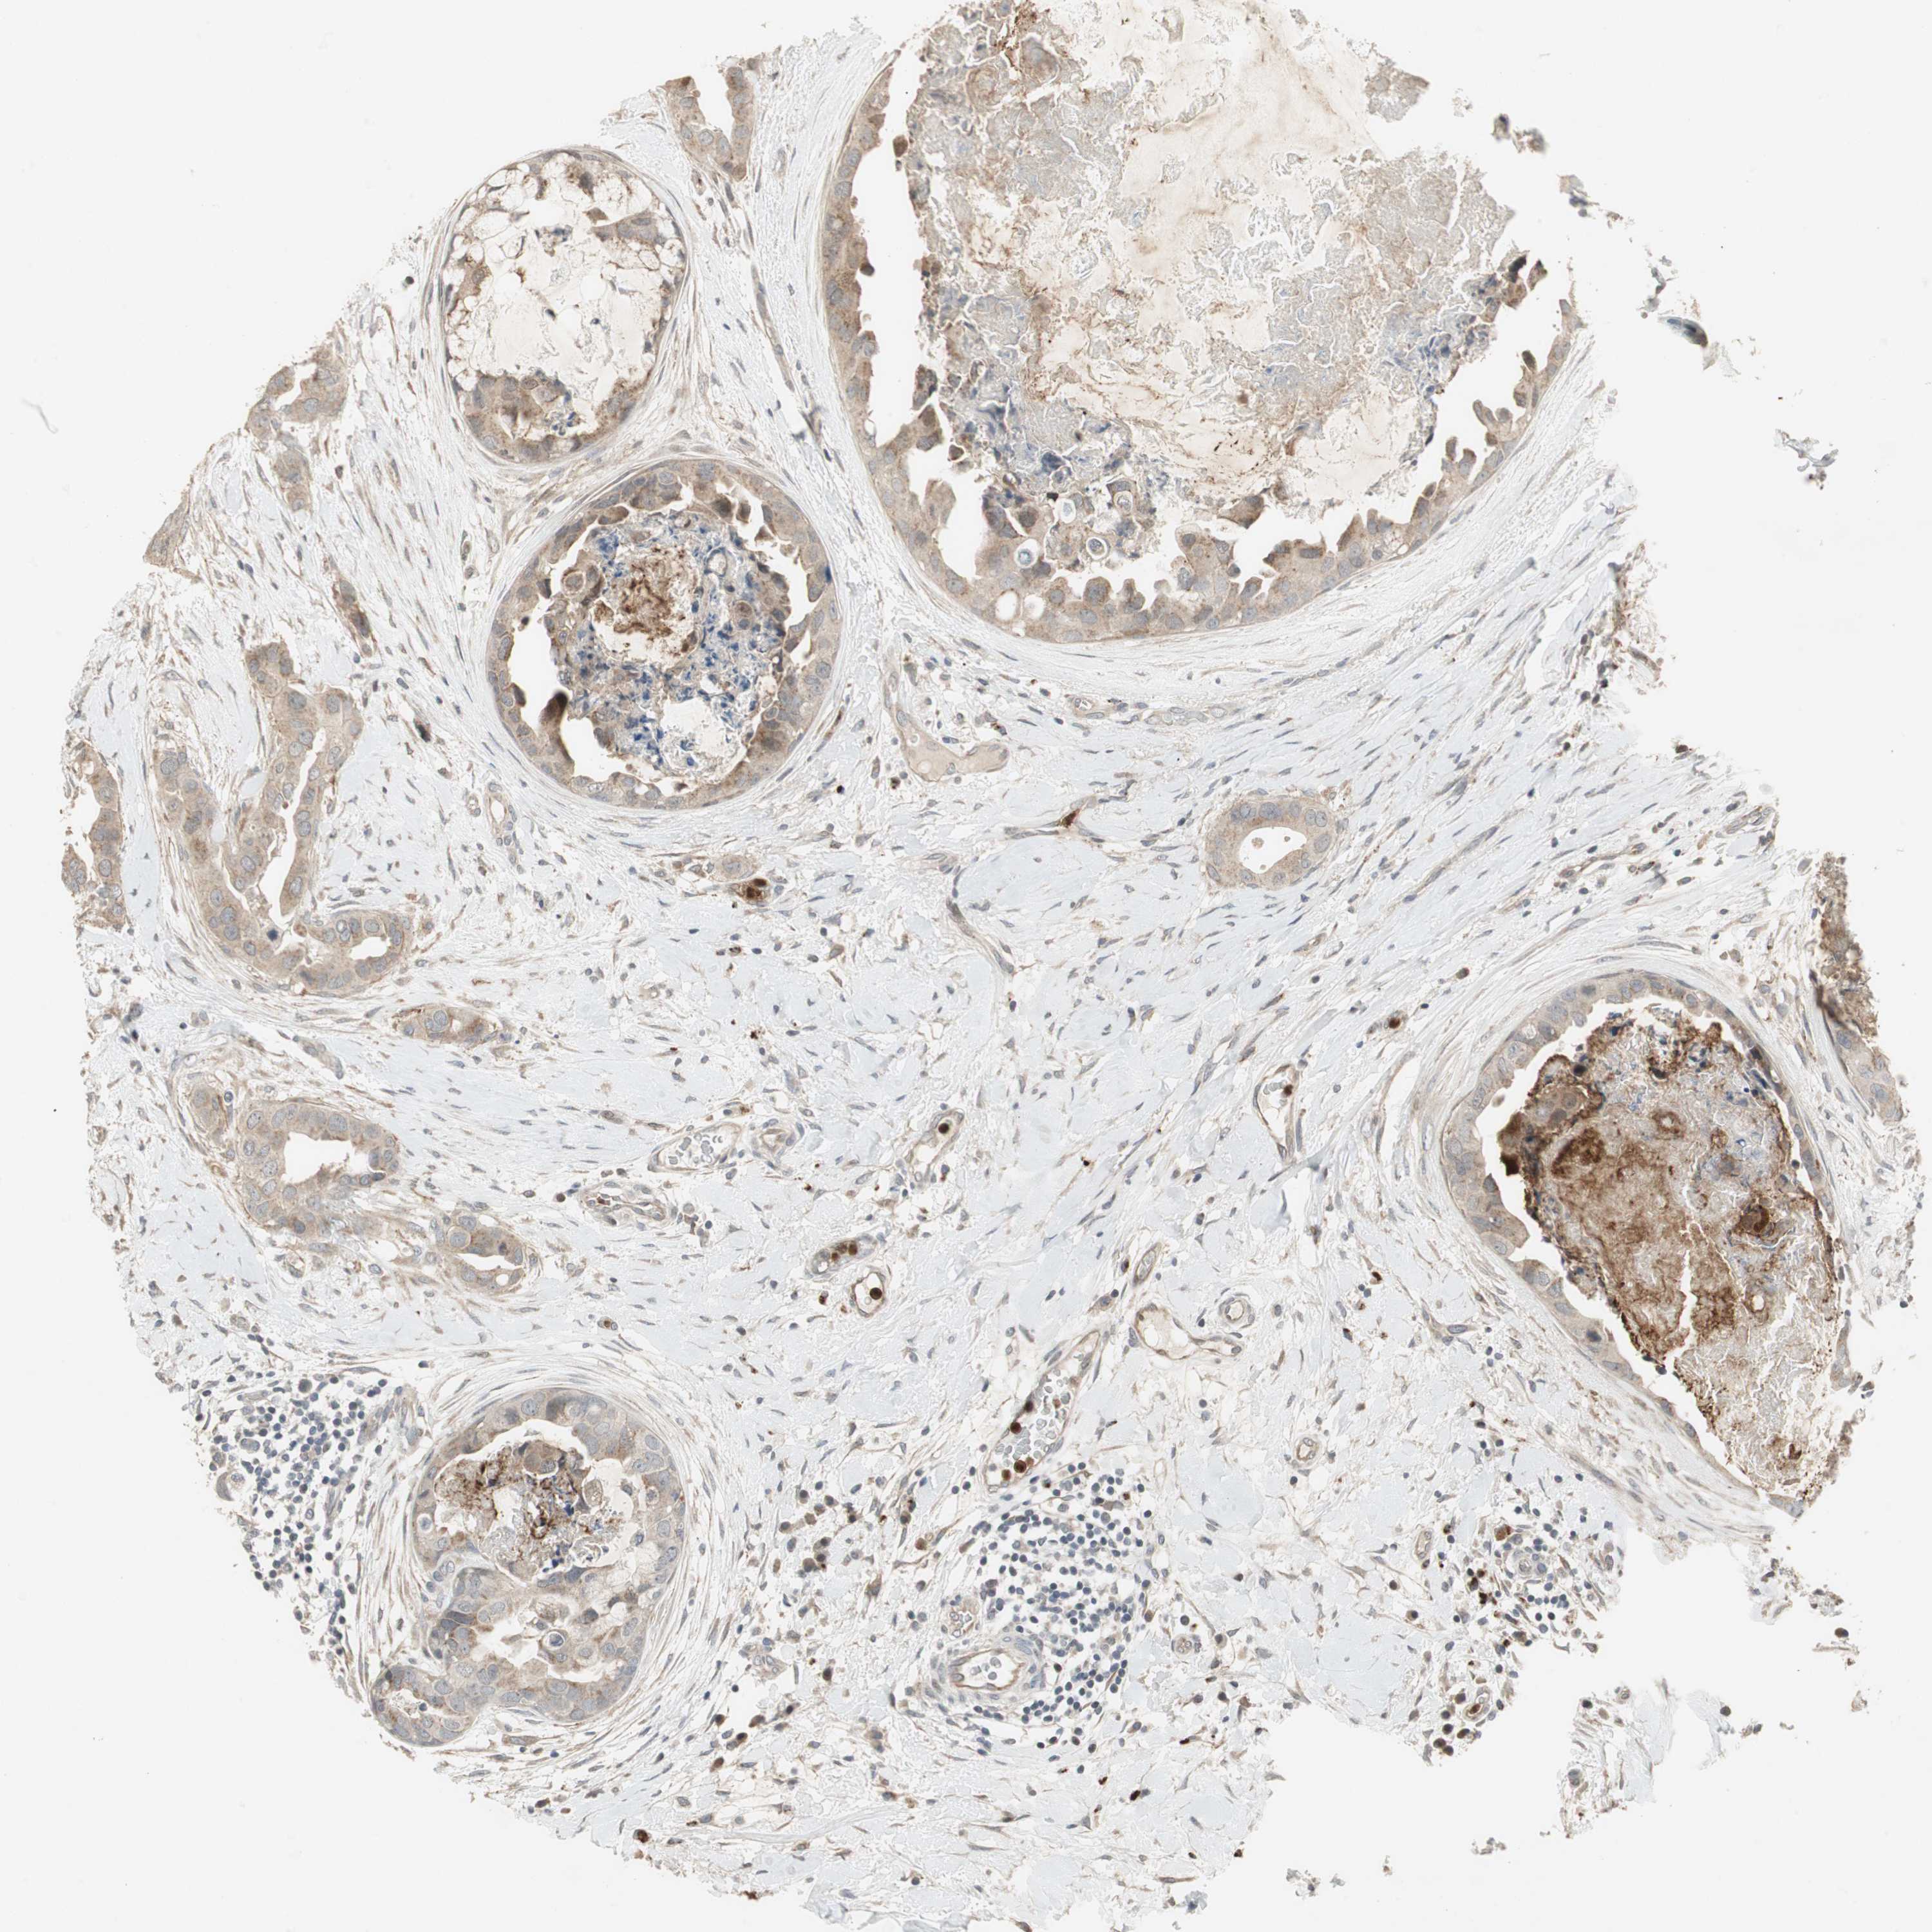

CANCER BREAST CANCER Show tissue menu

BRCA TCGA BRCA VALIDATION PROTEIN EXPRESSION